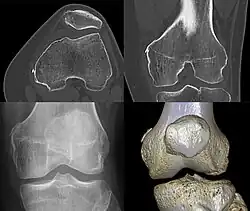

Different View of Pellegrini-Stieda Syndrome